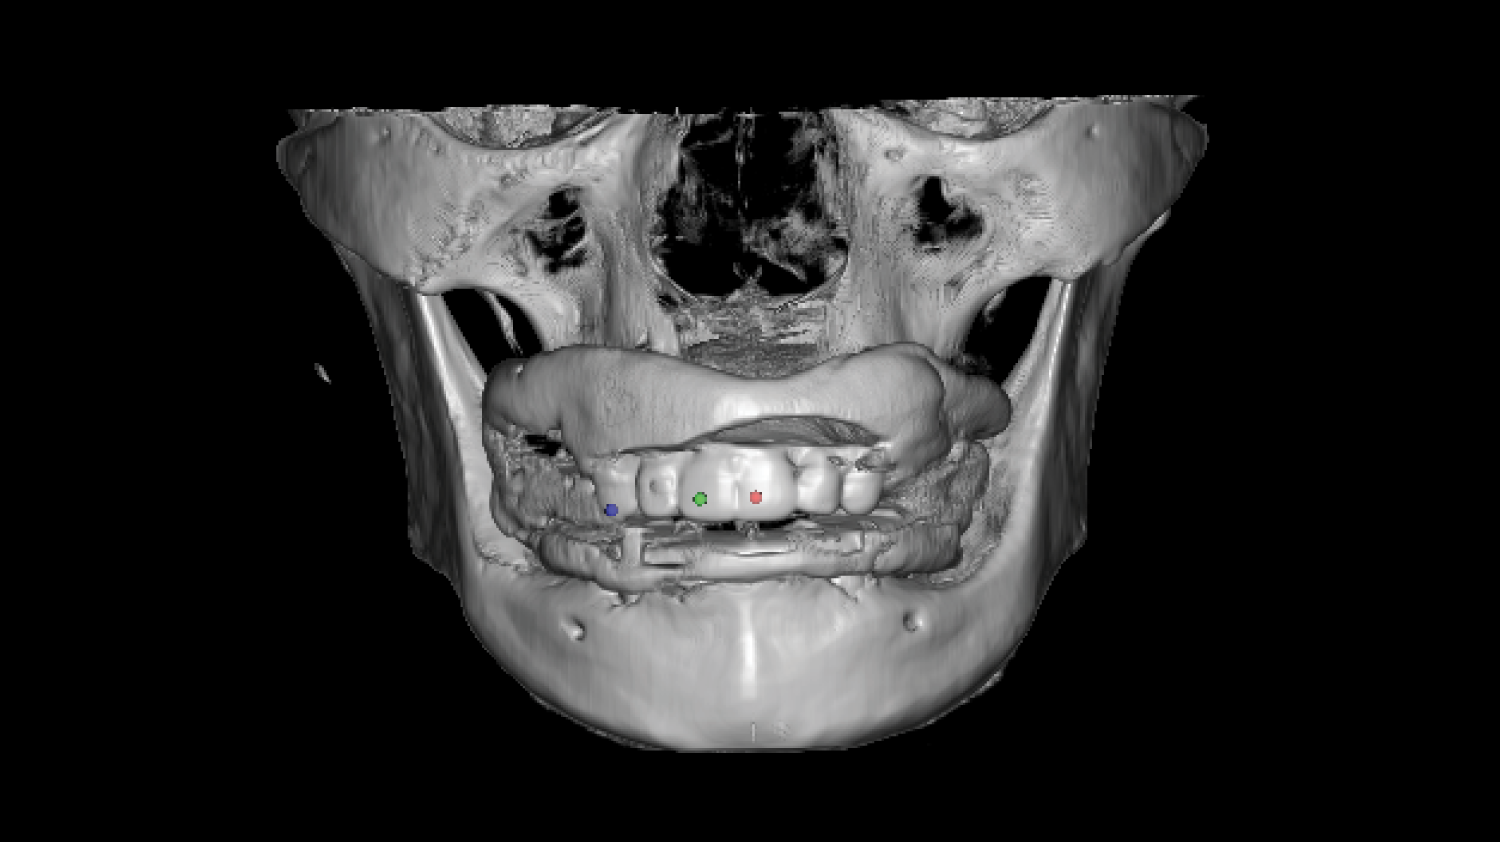

The program also introduces the JB Fork system, which integrates CBCT imaging and anterior reference points to enable one-step surgical stent fabrication without repeated impressions. Through practical demonstrations, attendees will see how this approach streamlines implant surgery while maintaining accuracy. The course concludes with insights into plasma surface treatment in implantology, highlighting its role in advancing clinical outcomes.

The program also introduces the JB Fork system, which integrates CBCT imaging and anterior reference points to enable one-step surgical stent fabrication without repeated impressions. Through practical demonstrations, attendees will see how this approach streamlines implant surgery while maintaining accuracy. The course concludes with insights into plasma surface treatment in implantology, highlighting its role in advancing clinical outcomes.

Part 2

One-Step Surgical Stent Fabrication with JB Fork

• Radiopaque JB Fork and the role of six anterior reference points: Registration with CBCT and integration with facial scanners

• One-step avatar creation without additional clinical procedures

• Surgical stent design and its application in implant surgery

• Live demonstration of JB Fork application in a patient case

JB fork application lecture (Prof Huh) |

| 03:30PM – 04:00PM |

Real patient application and taking CBCT, JB fork scanning(Prof Huh) |

| 04:00PM – 05:00PM |

Surgical stent design with all guides and implant studio software. (Prof Huh) |

Part 2

One-Step Surgical Stent Fabrication with JB Fork

• Radiopaque JB Fork and the role of six anterior reference points: Registration with CBCT and integration with facial scanners

• One-step avatar creation without additional clinical procedures

• Surgical stent design and its application in implant surgery

• Live demonstration of JB Fork application in a patient case

JB fork application lecture (Prof Huh)

03:30 PM – 04:00 PM

Real patient application and taking CBCT, JB fork scanning(Prof Huh)

04:00 PM – 05:00 PM

Surgical stent design with all guides and implant studio software. (Prof Huh)